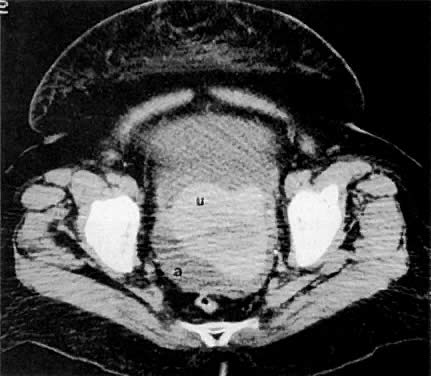

A 44-year-old woman with stage IB ovarian cancer. Axial CT scan of the pelvis shows bilateral complex cystic/solid ovarian masses (o). Despite contiguity to the uterus (u), there was no evidence of uterine invasion at surgery.

A 47-year-old woman with stage IB ovarian cancer. Axial CT scan of the pelvis shows large, bilateral cystic ovarian masses (o). Despite their size, the masses remain confined to the ovaries.